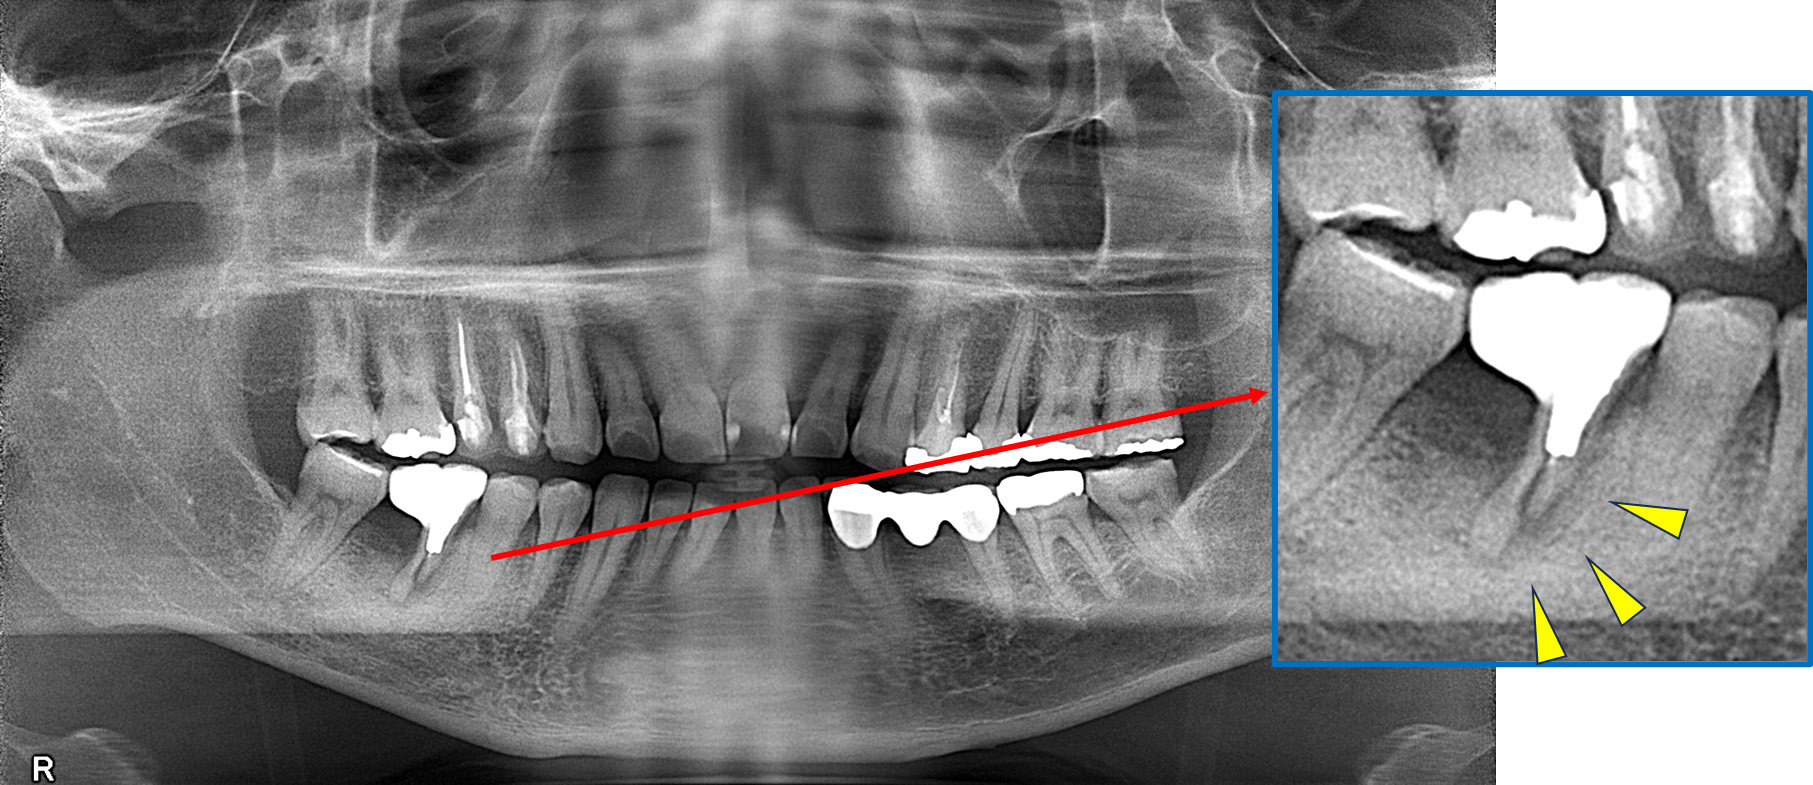

初診時

歯が割れていて、痛みがあり、抜歯となりました。

パノラマレントゲン写真 -

親抜歯後、歯ぐきは治癒しました。しかし、インプラント治療のためには骨が不足していました。

CT画像 -

骨移植(人工骨+メッシュプレート)を行い、骨を造りました。

インプラント手術を行いました。

手術の時に使用するサージカルステント

レントゲン画像 -

インプラント手術から3ヵ月後、型どりをして、仮歯を製作しました。

仮歯の調整期間を経て、セラミックの歯が入りました。

レントゲン画像 治療前 インプラント治療後

| 主訴 | 右下の歯が痛い。(抜歯後は、インプラント治療希望) |

| 診断 | 右下第一大臼歯 歯根膜炎 |

| 治療期間・通院回数 | 骨移植~インプラント治療 約1年(来院10回程度) |

| 治療費 | 骨移植 77,000円(税込) インプラント治療434,500円(税込) |